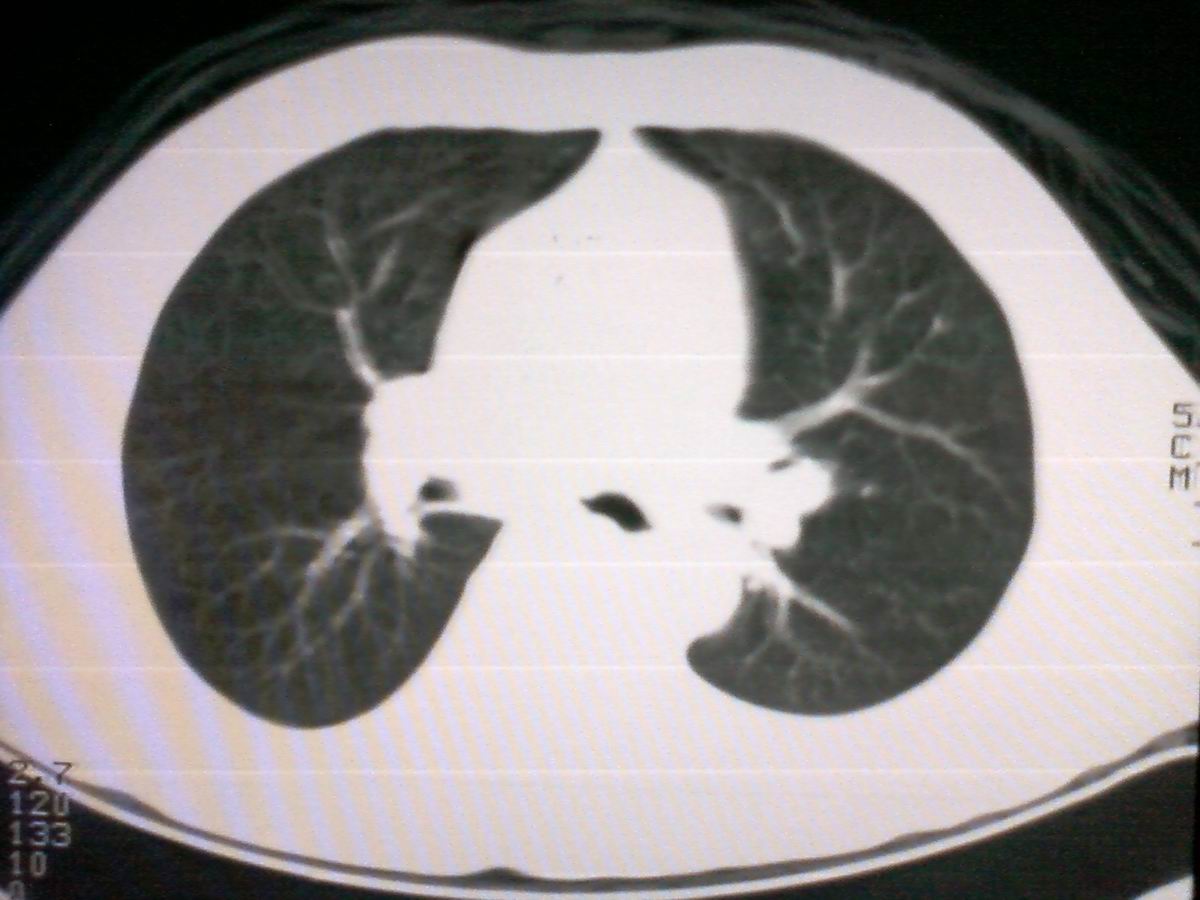

标题: CT25801:患者男性,65岁,临床提示双肺可闻及广泛罗音,看 [打印本页]

标题: CT25801:患者男性,65岁,临床提示双肺可闻及广泛罗音,看

支管占位,建议作支纤镜检查及活检。